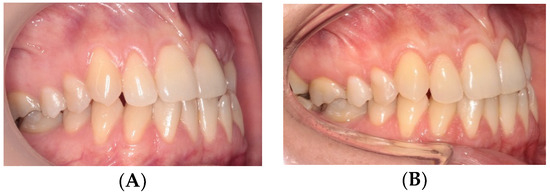

2.3. Surgical Procedures